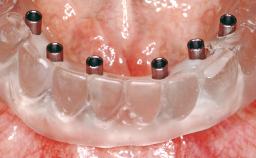

Immediate Loading of Six Implants in the Maxilla and Final Restoration with a Full-Arch CAD/CAM Zirconia FDP

# of Implants 6

Modality 6+ implants with immediate loading

Loading Protocol Immediate